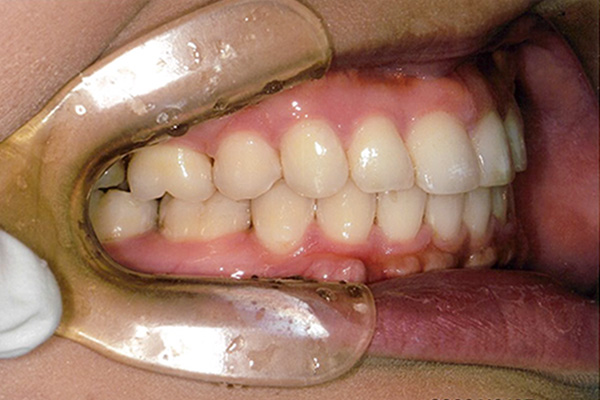

| 症状 | 下顎第一大臼歯の欠損 |

| 想定されるデメリット | 臼歯の近心移動が非常に難しい。高度なテクニックが必要である。 3D-LST矯正治療法を用い、抜歯を最小限に抑えながら歯の近心移動を実施。 |